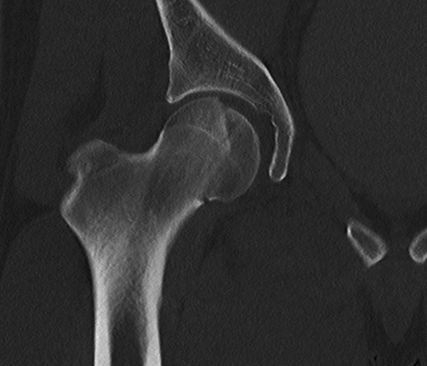

Abb. 1: Neben der klinischen Erstuntersuchung und Anamnese umfasst die Diagnostik die konventionelle native Röntgendiagnostik des verletzten Hüftgelenkes mit Standardaufnahmen im a.-p. und axialen Strahlengang. Abgebildet wird die erste Röntgenaufnahme (Hüftübersicht) nach Einlieferung in den unfallchirurgischen Schockraum nach Verkehrsunfall

Abb. 2: Ergänzend zur anterior-posterioren Aufnahme bedarf es einer axialen Röntgenaufnahme. Deutlich sichtbar ist das dislozierte Fragment des Femurkopfes rechts

Neben der klinischen Erstuntersuchung und Anamnese umfasst die Diagnostik die konventionelle native Röntgendiagnostik des verletzten Hüftgelenkes mit Standardaufnahmen im a.-p. und axialen Strahlengang (Abb. 1, 2) sowie gegebenenfalls die Anfertigung von Ala- und Obturatoraufnahmen. Obligatorisch empfehlen wir die Anfertigung eines Hüftübersichtsröntgens und gegebenenfalls, sofern möglich, auch eine Faux-Profil-Aufnahme. Zur präoperativen Planung und zur Beurteilung des Repositionsergebnisses ist der Goldstandard die Computertomografie (Abb. 3) mit Anfertigung einer 3D-Rekonstruktion. Im Rahmen der Notfalldiagnostik spielt die Magnetresonanz keine wesentliche Rolle. Im Hinblick auf die Diagnostik sekundär auftretender Komplikationen ist jedoch die Bedeutung des MRT unumstritten.